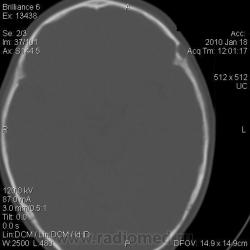

Ребёнок коллеги из нашей больницы, 1 г. 9 мес. С 1,5 месячного возраста отмечали небольшую припухлось в левой теменно-височной области, которая постепенно увеличивалась с ростом ребёнка. Припухлость расценивалась как лимфоузел, однако в связи с длительным характером процесса решили дообследовать. Доктор, выполнявший УЗИ, сообщил, что на лимфоузел это не похоже, и он не видит кости под образованием. Выполнили рентгенографию, затем - КТ.

Полной ясности нет. Мы думаем о: 1. Эозинофильной гранулёме.

2. Дермоидной кисте? Фиброме? Др. мягкотканной опухоли?, которая, постепенно оказывая давление на кость, вызвала атрофию костной ткани.

3. Каком-то врождённом нарушении оссификации кости черепа?

Наиболее вероятен дермоид. Округлый костный дефект с четкими ровными контурами - атрофия от давления. Дефект в наружной пластике больше, чем во внутренней (блюдцеобразный дефект). Плотность образования вероятно жировая. Локализация на границе швов также более характерна для дермоида. Фибромы гораздо плотнее, вряд ли вызовут атрофию от давления, никогда не слышала о таком, доброкачественным опухолям проще расти кнаружи, чем разрушать кость. Часто фибромы достигают значительных размеров и не вызывают атрофию от давления. Интересно образование плотное или мягкое, четко отграниченное, с гладкой поверхностью?

Безболезненность и плотность образования говорит в пользу дермоида. Контуры нечеткие? А как же сравнения с лимфоузлом? Возможно контуры скрадывают мягкие ткани головы, тем более само образование маленькое. Если КТ делали у Вас, попросите измерить плотность. А контуры дефекта действительно гладкие, подчеркнутые? Я не ошибаюсь? Не очень хорошо видно на КТ, слишком мелко.

Контуры гладкие. Плотность от 14 до 27 HU.

Я тоже думаю, что больше данных за дермоид.

Согласен с версией дермоид; в образовании есть участки низкой плотности сопоставимыми с плотностью жира, что является характерным признаком при дермоидах.

Спасибо, коллеги, за помощь. Похоже, это действительно дермоидная киста.